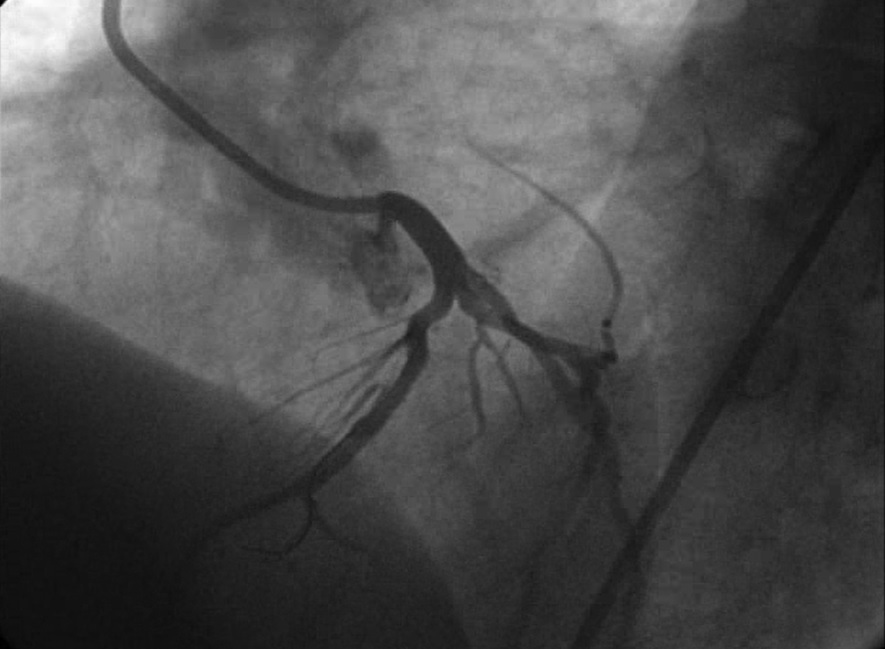

Anjinapektoris aşamasında yapılan anjiografide sıklıkla %50 üzerinde darlıklar saptanır ve balon/stent işlemi ile açılır. Kalp krizi geçirende yani damarın %100 tıkandığı vakalarda ağrı başlangıcından itibaren ilk 90 dakika içinde balon/stent işlemi yapılarak tıkalı damar açılmalıdır, aksi takdirde bu tıkalı damarın kanlandırdığı sahada kalıcı doku ölümü yaşanacaktır.

- Koroner Anjiografi ve Balon/Stent İşlemi

- Kronik Tam Tıkalı Kalp Damarında Balon/Stent İşlemi

- Ana Dal ile Birlikte Yan Dal(lar)ı da Tutan Çatal Lezyonlarda (daralma) Balon/Stent İşlemi